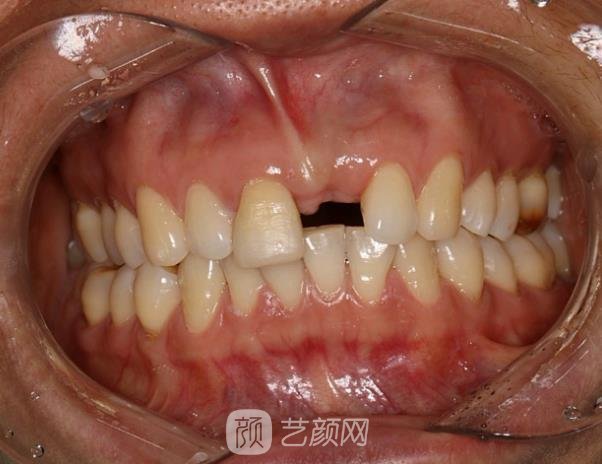

種植牙案例:

對(duì)于我這個(gè)年紀(jì)來(lái)說(shuō),種植牙其實(shí)并不適合我,畢竟沒有哪個(gè)人年紀(jì)輕輕就掉牙的,但我就是一個(gè)例外,一場(chǎng)意外導(dǎo)致我的牙掉了,當(dāng)時(shí)我心情壞到了極點(diǎn),畢竟缺了一顆牙,對(duì)誰(shuí)都不好受。

為了遮掩這個(gè)缺陷,我的笑容也減少了,幸好這段時(shí)間都戴口罩,我這個(gè)缺陷大家都看不見,平時(shí)如果實(shí)在忍不住,都會(huì)用手進(jìn)行遮掩,所以大家都說(shuō)我變得含蓄內(nèi)向了,整個(gè)人的給人的形象發(fā)生了很大的變化。

為了回歸本性,我較終選擇了種植牙,當(dāng)時(shí)在一番了解后發(fā)現(xiàn),種植牙的價(jià)格蠻高,所以在選擇的時(shí)候尤為謹(jǐn)慎,較終我選擇當(dāng)?shù)氐暮D厢t(yī)學(xué)院第一附屬醫(yī)院,這家醫(yī)院的口腔科在當(dāng)?shù)刂群芨?,所以選擇這家我還是較為放心的。

慢慢的,種植牙部位的傷口也恢復(fù)好了,從外表看不出任何不同,牙齒完全沒有色差,看起來(lái)渾然一體,現(xiàn)在也可以放心大笑了,完全不用遮遮掩掩了,身邊的朋友都說(shuō)以前的我回來(lái)了。